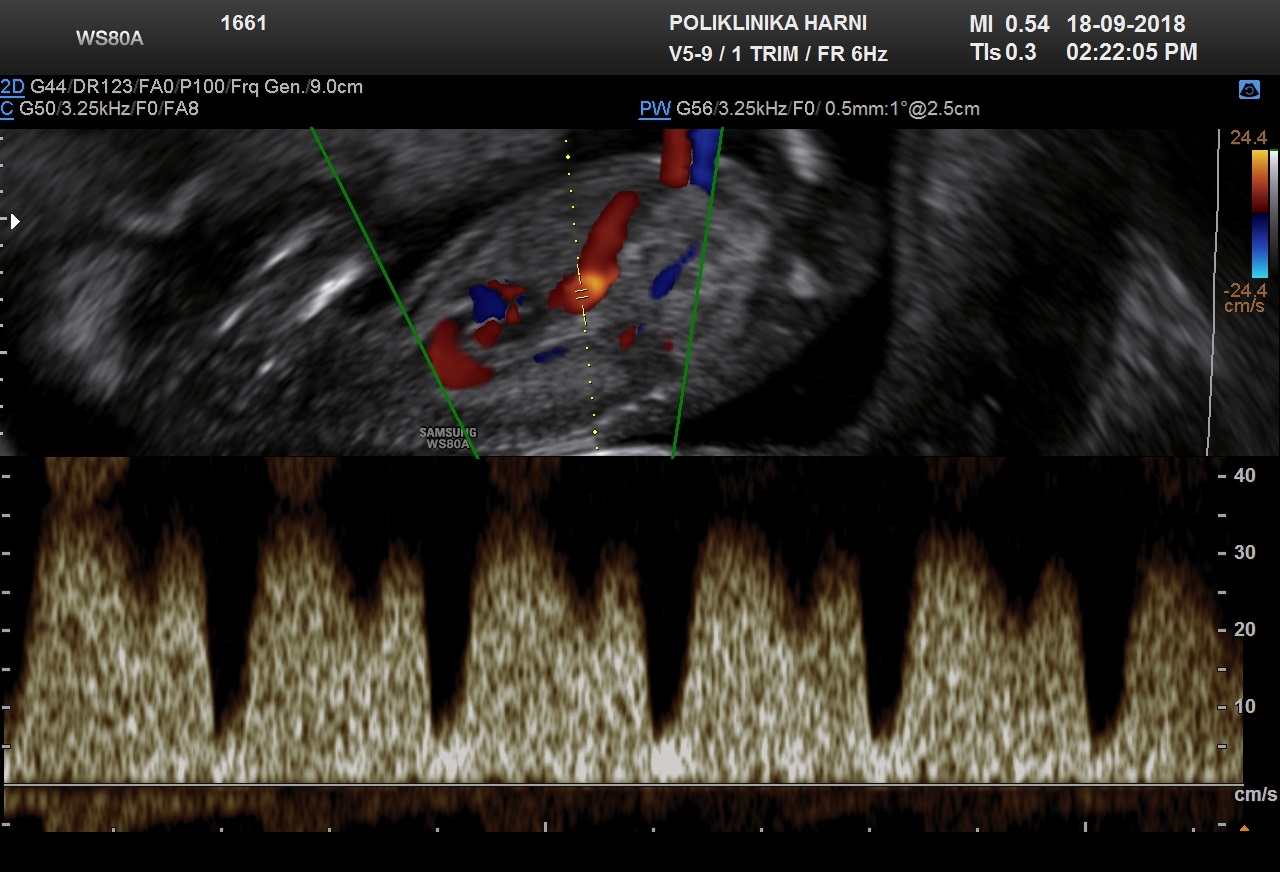

Duktus venozus krvna je žila koja nastaje u 6. tjednu trudnoće nakon obliteracije kompletne desne umbilikalne vene, kranijalnog dijela lijeve umbilikalne vene, lijeve žumanjčane vene i dijela jetrenih anastomoza. Ova krvna žila postaje poveznica - shunt između lijeve umbilikalne vene i desnog hepatokardinalnog kanala. Protok kroz duktus venozus ima karakterističnu krivulju na doplerskom sonogramu: prvi val je brzi pozitivni protok za vrijeme sistole ventrikula, drugi je nešto manje brzine za vrijeme dijastole ventrikula, a treći je i dalje pozitivan protok tijekom atrijske kontrakcije. Ultrazvučno možemo prepoznati povećani otpor u duktusu venozusu kao i izostanak dijastoličkog protoka ili povratni protok u vrijeme kontrakcije atrija, te veće razlike između sistole i dijastole.

S obzirom da protok u duktusu venozusu predstavlja izravni gradijent tlakova između umbilikalne vene i desne pretklijetke, dodatno se može prepoznati i izostanak dijastole te povratni protok u donjoj šupljoj veni i pulsacije u umbilikalnoj veni, koje odgovaraju kontrakciji atrija. Sukladno teorijama o razvitku nakupljanja tekućine u nuhalnoj regiji, poremećaj priljeva / preload i odljeva / afterload može nastati zbog prevelikog opterećenja zbog dotoka povećanih količina cirkulirajućih tjelesnih tekućina, ali isto tako i zbog poremećenog protoka, odnosno propustljivosti krvi kroz srce u fetusa sa zastojnim srčanim greškama. Oba stanja dovode do venskog zastoja i povišenog otpora koji prepoznajemo po povratnom protoku u duktusu venozusu već u prvom tromjesečju. Takav nalaz između 11.- 14. tjedna povezan je s kromosomopatijama, anomalijama srca i lošim ishodom trudnoće.

Nedostatak protoka / zero flow ili absent flow ili negativan protok / inversed flow u duktusu venozusu tijekom atrijske kontrakcije nalazi se u 80% fetusa s kromosomskim abnormalnostima, uz oko 5% fetusa s normalnim kariogramom. Kako nije dokazana veza između patološkog protoka u ductusu venosusu i povećanog nuhalnog nabora, paralelno ispitivanje oba faktora povisuje stopu detekcije trisomije 21 na 94%. Otuda je pregled protoka kroz duktus venozus tehnikom obojenog Dopplera sastavni dio svakog ozbiljnijeg traganja za ultrazvučnim biljezima kromosomopatija.